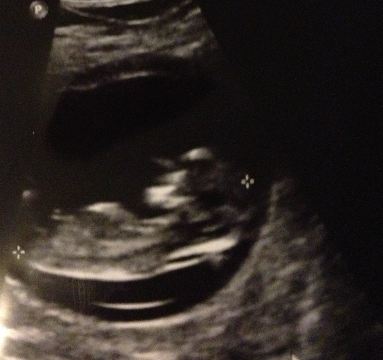

hope you don't mind i have just rotated it as its easier to guess on

Attachment 10584

not sure about a guess, looks straight to spine but there is something on top so if its early 12th week it maybe on the way up

You can't see the whole nub... So I would guess 50/50

Thinking boy because of the bit on top

I don't think I see a nub at all I think that lil nub looking thing is cord its high up on the belly!